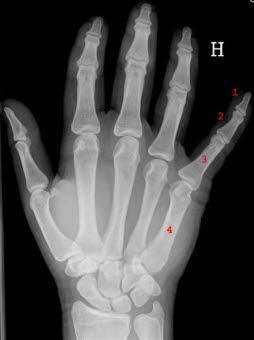

HåndskjelettTommelartrose er en ganske vanlig tilstand og ses især hos eldre og middelaldrende kvinner. Tilstanden forekommer også hos yngre mennesker, særlig dersom det tidligere har vært skader eller sykdom i leddet.

Ved røntgen-undersøkelse ser en de karakteristiske slitasjeforandringene med nedslitt/tynn brusk og eventuelt forkalkninger inn mot leddet.